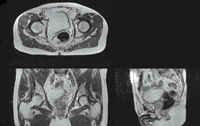

Thirty-nine patients undergoing prostate radiotherapy have had whole pelvic T2-weighted MRI scans, in addition to standard small-field-of-view MRI scans and conventional radiation therapy CT scans. The contours of the bladder, rectum, bone and prostate were manually delineated on each MRI and CT dataset.

Probabilistic atlas-based organ segmentation methods were developed to automatically segment the organs of interest (prostate, rectum, bladder, and femoral heads) from the MRI scans. After the scans were preprocessed (including correction of intensity inhomogeneity8 and patient movement artefacts9), the images and manually defined contours for each patient were combined into a single reference atlas by image registration methods. This atlas can then be warped onto the MRI scans of a new patient, automatically contouring the organs of interest (Box 3). A matching CT atlas enables the automatic estimation of electron densities from MRI scans by the same method.